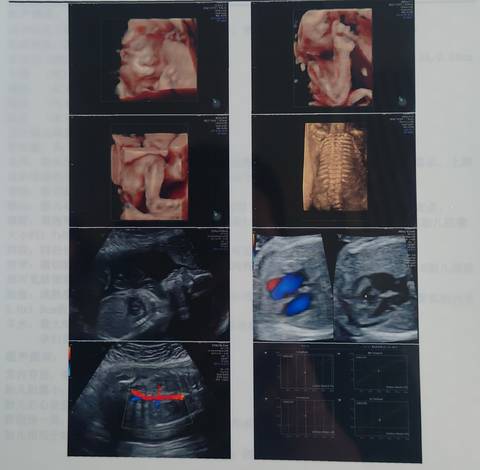

四维通过,感觉是女儿,你们给看看!

神采飞扬的 2021-12-18 11:47

亲,我们都是一样觉得好奇,确实没什么依据,不要想太多,生下来最准确的,一切顺利!

看不出来,这个单上的数据是很难直接判断男孩还是女孩的哦,其实只要孩子健健康康就好,生下来才最准

你好。我们是判断不了男宝宝跟女宝宝的,孕期定期检查,我觉得宝宝健康就好的。祝心想事成 。

#妈妈问答大赛#哈哈,愿心想事成,接女宝。一般都说胎心率高的是女孩,胎心率高的是男孩